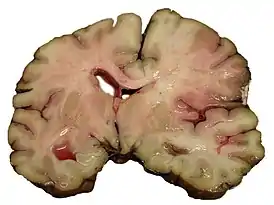

![]() Срез мозга человека, умершего от инсульта | |